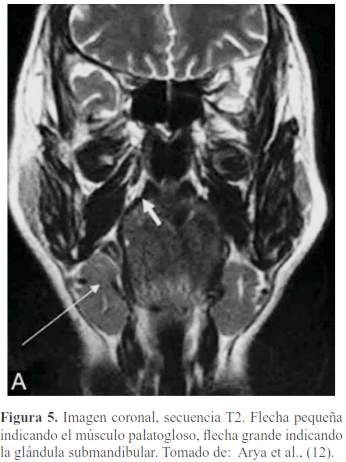

El paladar blando está formado por 5 músculos a cada lado, insertados en el velo, formados de adelante hacia atrás vistas mediante RM (10) (figura 5, figura 6, figura 7, figura 8 y figura 9):

Glosoestafilino o Palatogloso (a veces incluido en músculos de la lengua).